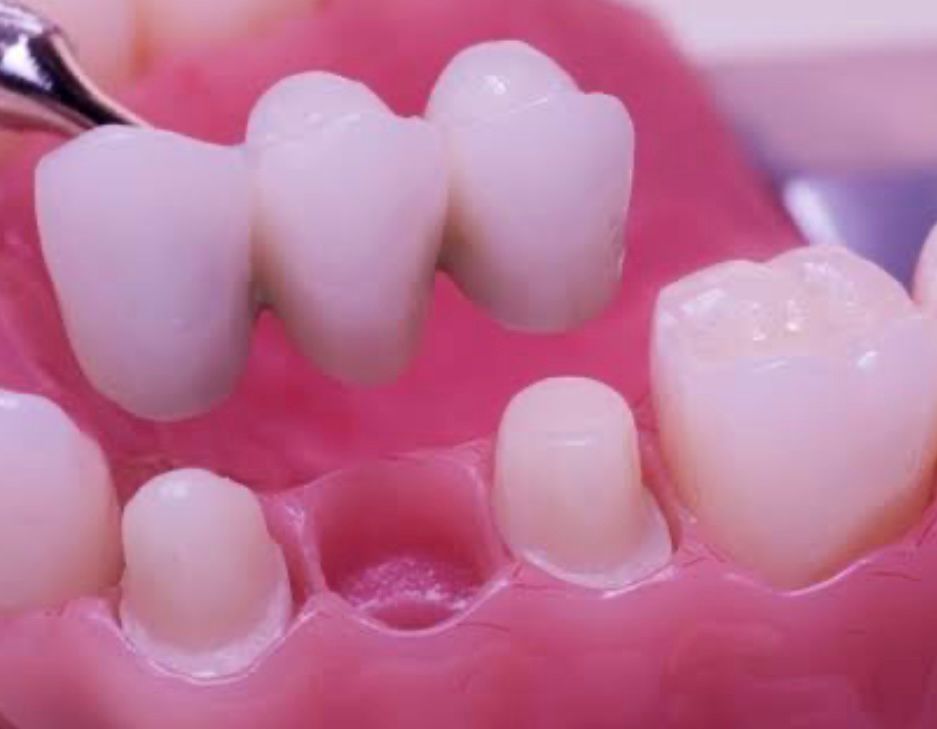

Prothèses dentaires

Restauration des dents manquantes avec des solutions fixes ou amovibles.